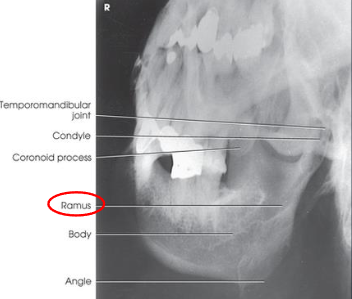

Axiolateral and axiolateral oblique mandible

goal is to place desired portion of the madible parallel with the IR

patient position:

upright in anterior oblique position, semiprone, or semisupine

part position:

head lateral with IPL perpendicular to IR

mouth closed with teeth together

extend neck to place mandibular body parallel with transverse axis of IR

adjust rotation of head to place area of interest parallel to IR

ramus: head in true lateral

body: rotate head 30 degrees toward IR

symphysis: rotate head 45 degrees toward IR

respiration suspended

CR:

25 degrees cephalad, passes directly through mandibular region of interest

collimation:

1 inch beyond the anterior and inferior skin shadows and above the TMJ

Axiolateral and axiolateral oblique mandible image criteria

shows region of the mandible that was parallel with the IR: ramus, body, or symphysis

ramus and body:

no overlap of the ramu sby opposite side of mandible

no elongation or foreshortening of ramus or body

no superimposition of the ramus by the cervivcal spine

symphysis:

no overlap of the mentum region by the opposite side of the mandible

no foreshortening of the mentum region